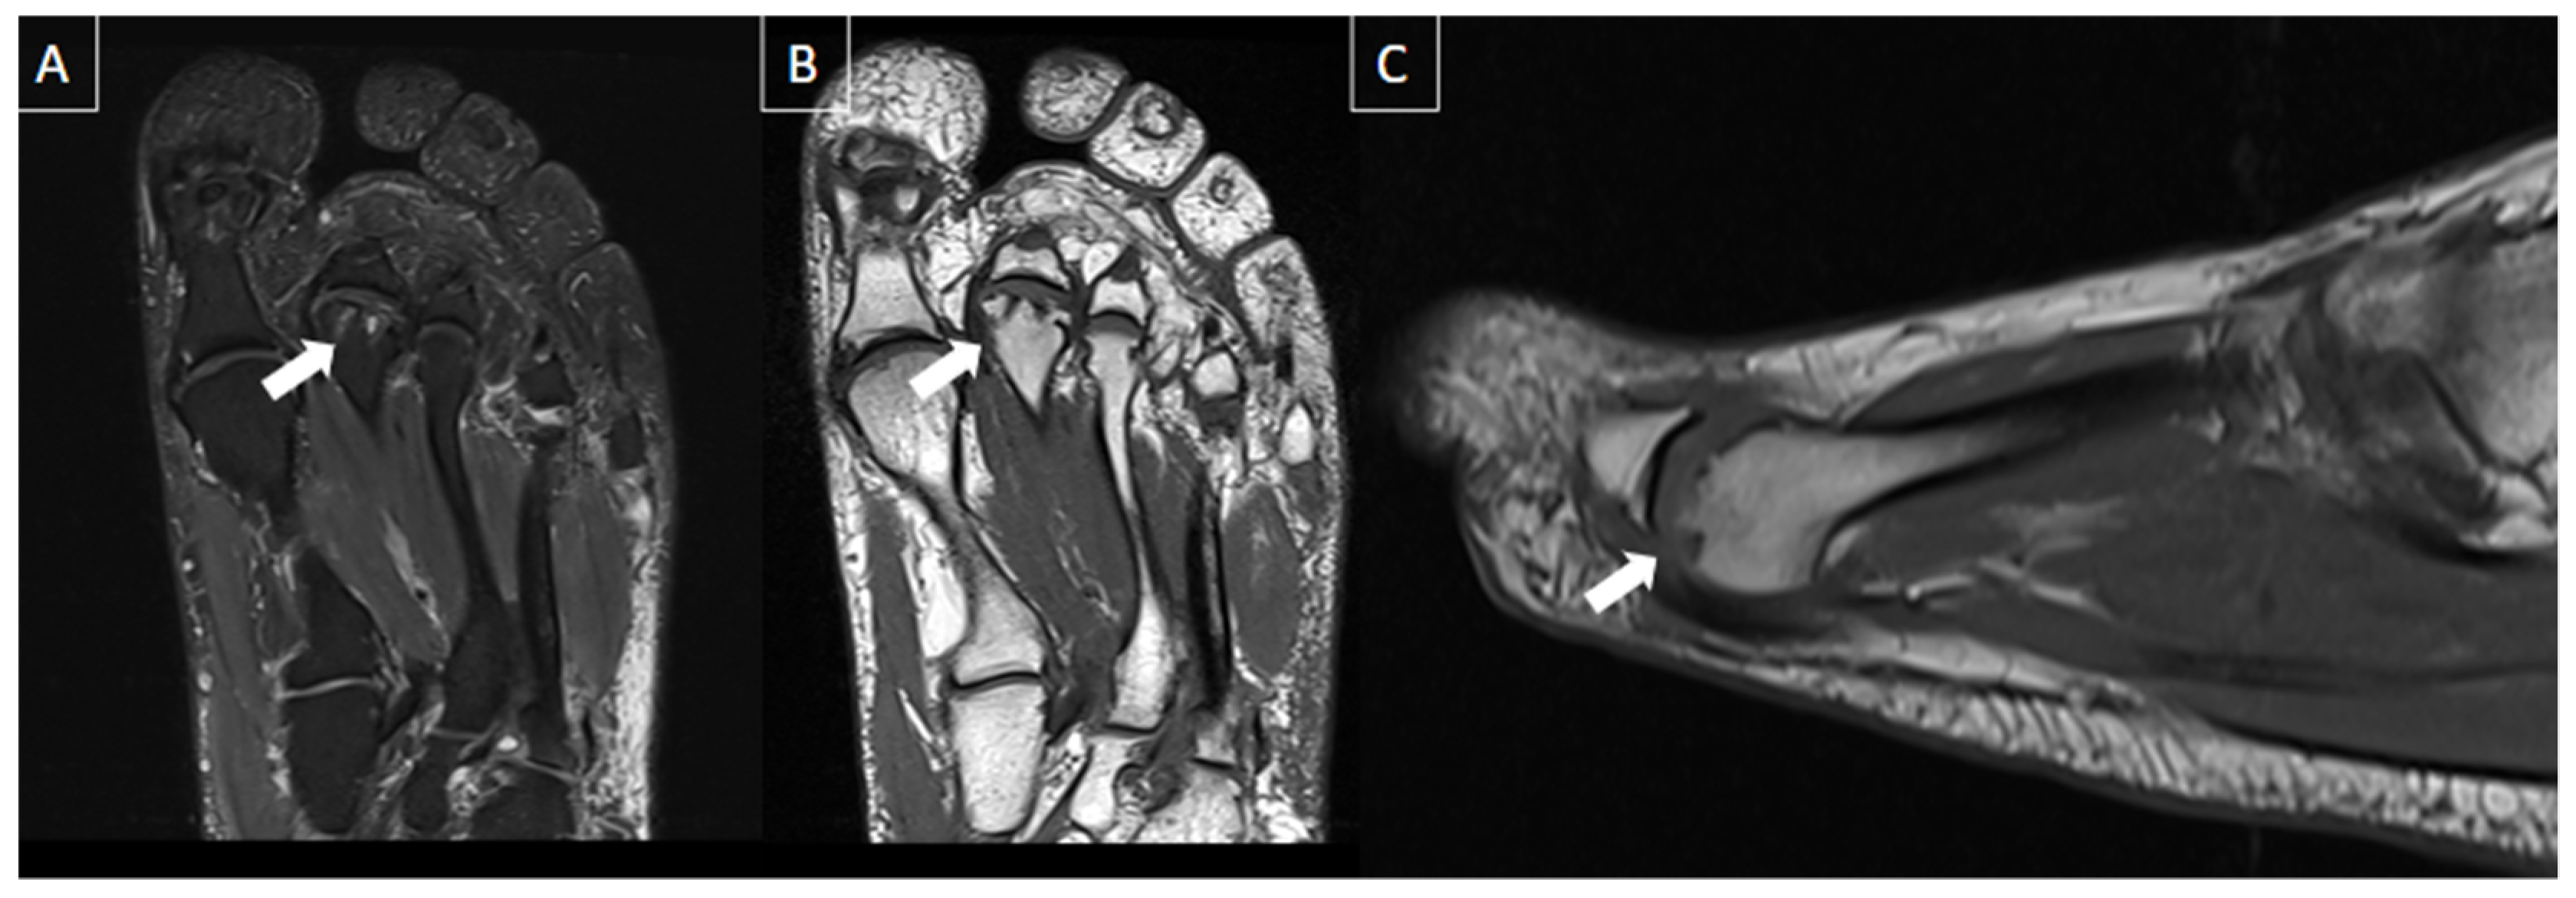

6.5. Plantar Fibromatosis